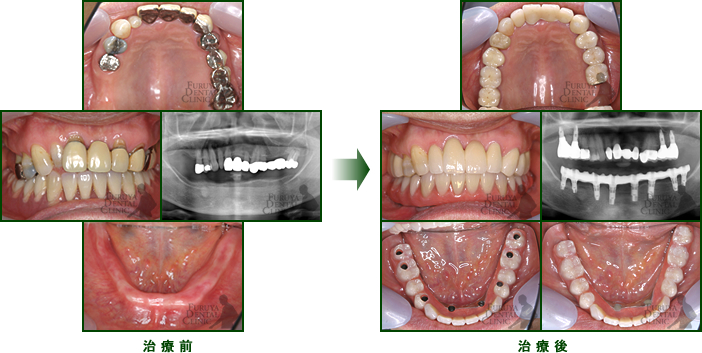

70代 女性

前歯、臼歯部に広範囲に欠損があり全体的咬合崩壊を起こしつつある症例。

歯周治療、補綴治療、インプラント治療で再構築